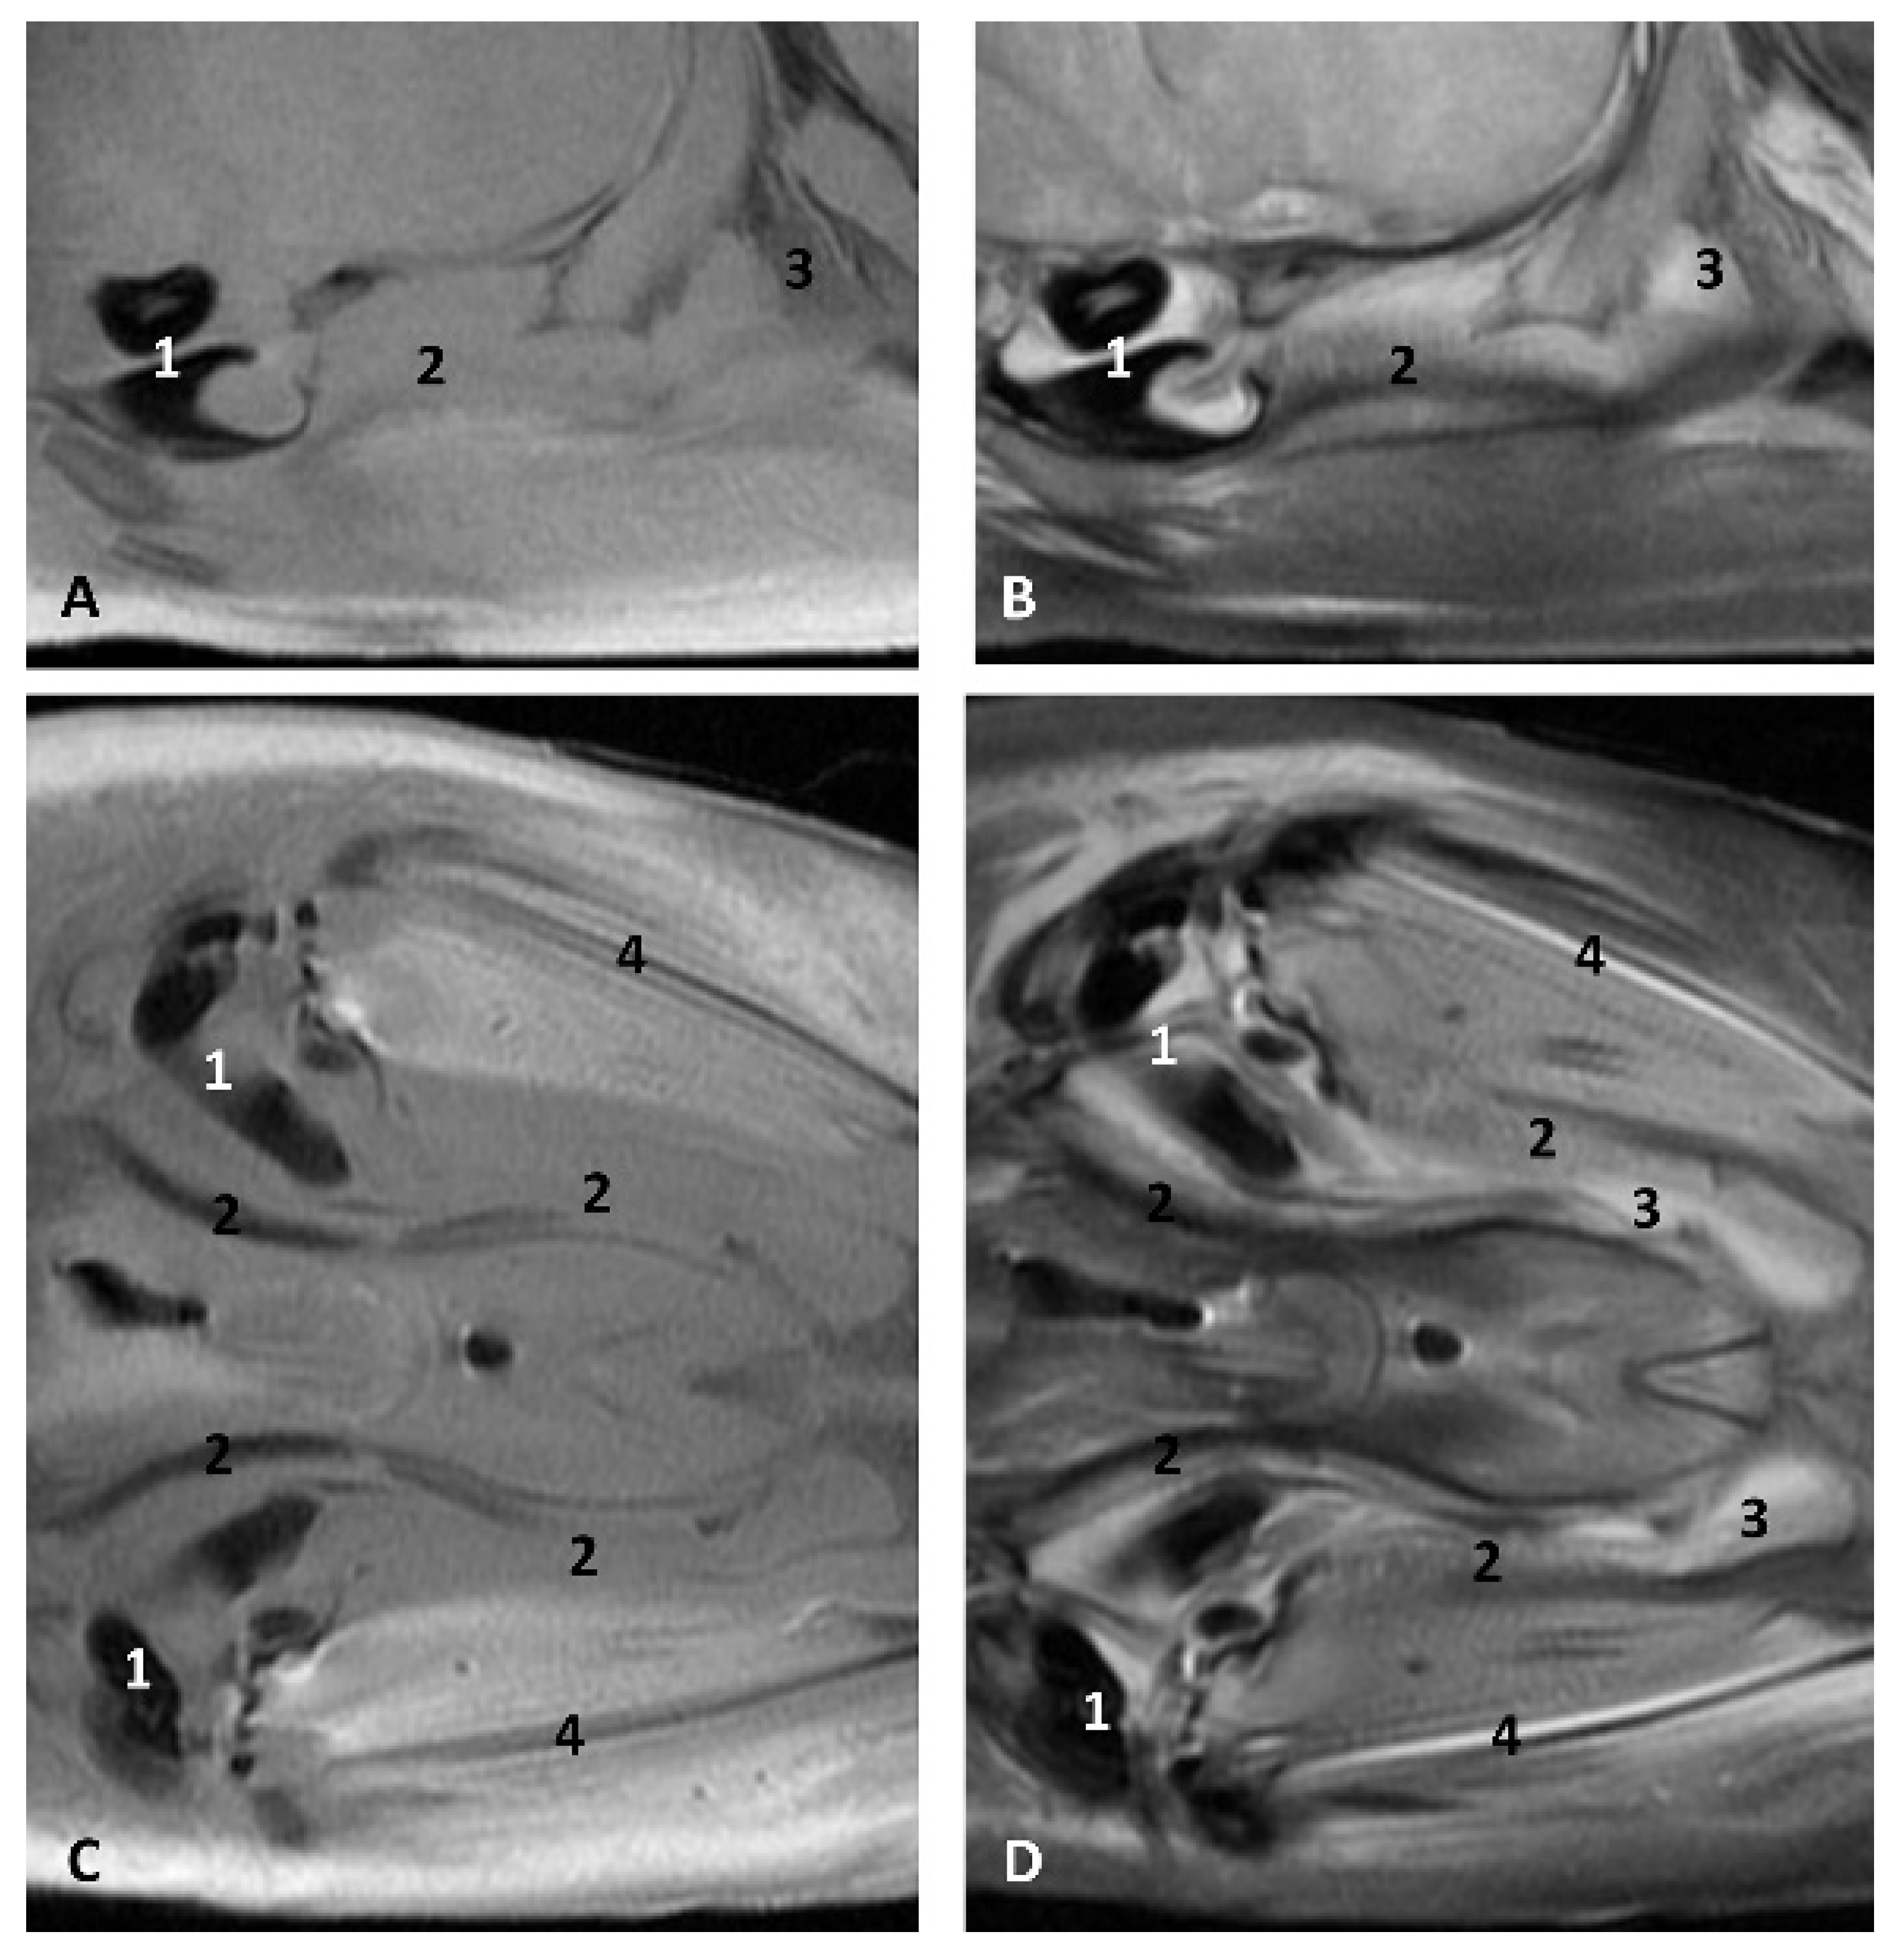

The MRI sagittal images show a pharyngeal cavity in a Globicephala melas fetus (gma1) and we could appreciate the oropharynx (fauces), the nasopharynx and the oesophageal vestibule hypointense in both T1 and T2 sequences(Figure 25A,B). Coronal T1 and T2 sequences show the piriform recess alongside the larynx (Figure 25C,D).

Figure 25.

Images of the oral and pharyngeal cavity. MR sagittal and coronal images are oriented so that the rostral is to the right. (A) T1 SE sagittal, (B) T2 FrFSE sagittal, (C) T1 SE coronal and (D) T2 FrFSE coronal planes. 5 months, gma1. 1, Hard palate; 2, Tongue; 3, Oral cavity (closed); 4, Oropharynx: fauces; 5, Oropharynx: soft palate; 6, Laryngopharynx: left piriform recess; 7, Laryngopharynx: oesophageal vestibule; 8, Epiglottis cartilage; 9, Epiglottic vallecula; 10, Arytenoid cartilages; 11, Nasopharynx; 12, Larynx.